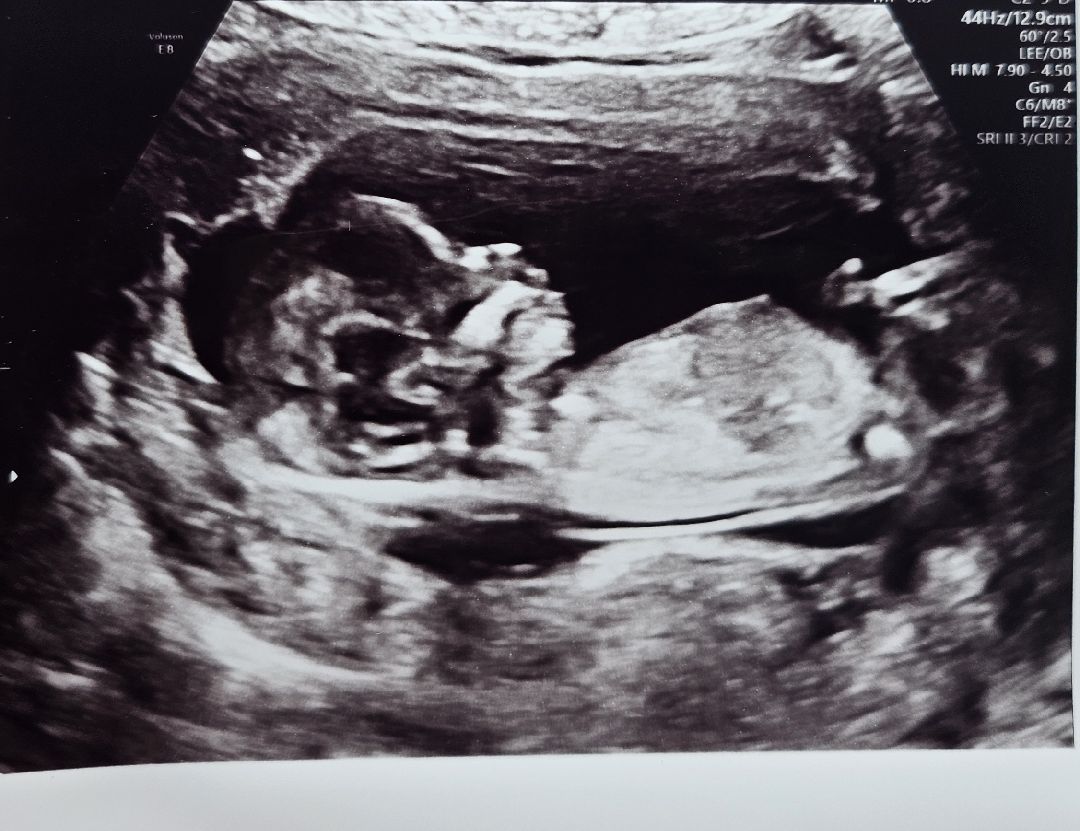

딸일까 아들일까 너무 궁금한데.. 아무리 각도법 찾아보아도 잘모르겠네요 ㅠㅠ 이 사진으로도 성별 알수 있을까요? 각도법 확인 부탁드립니다🫶